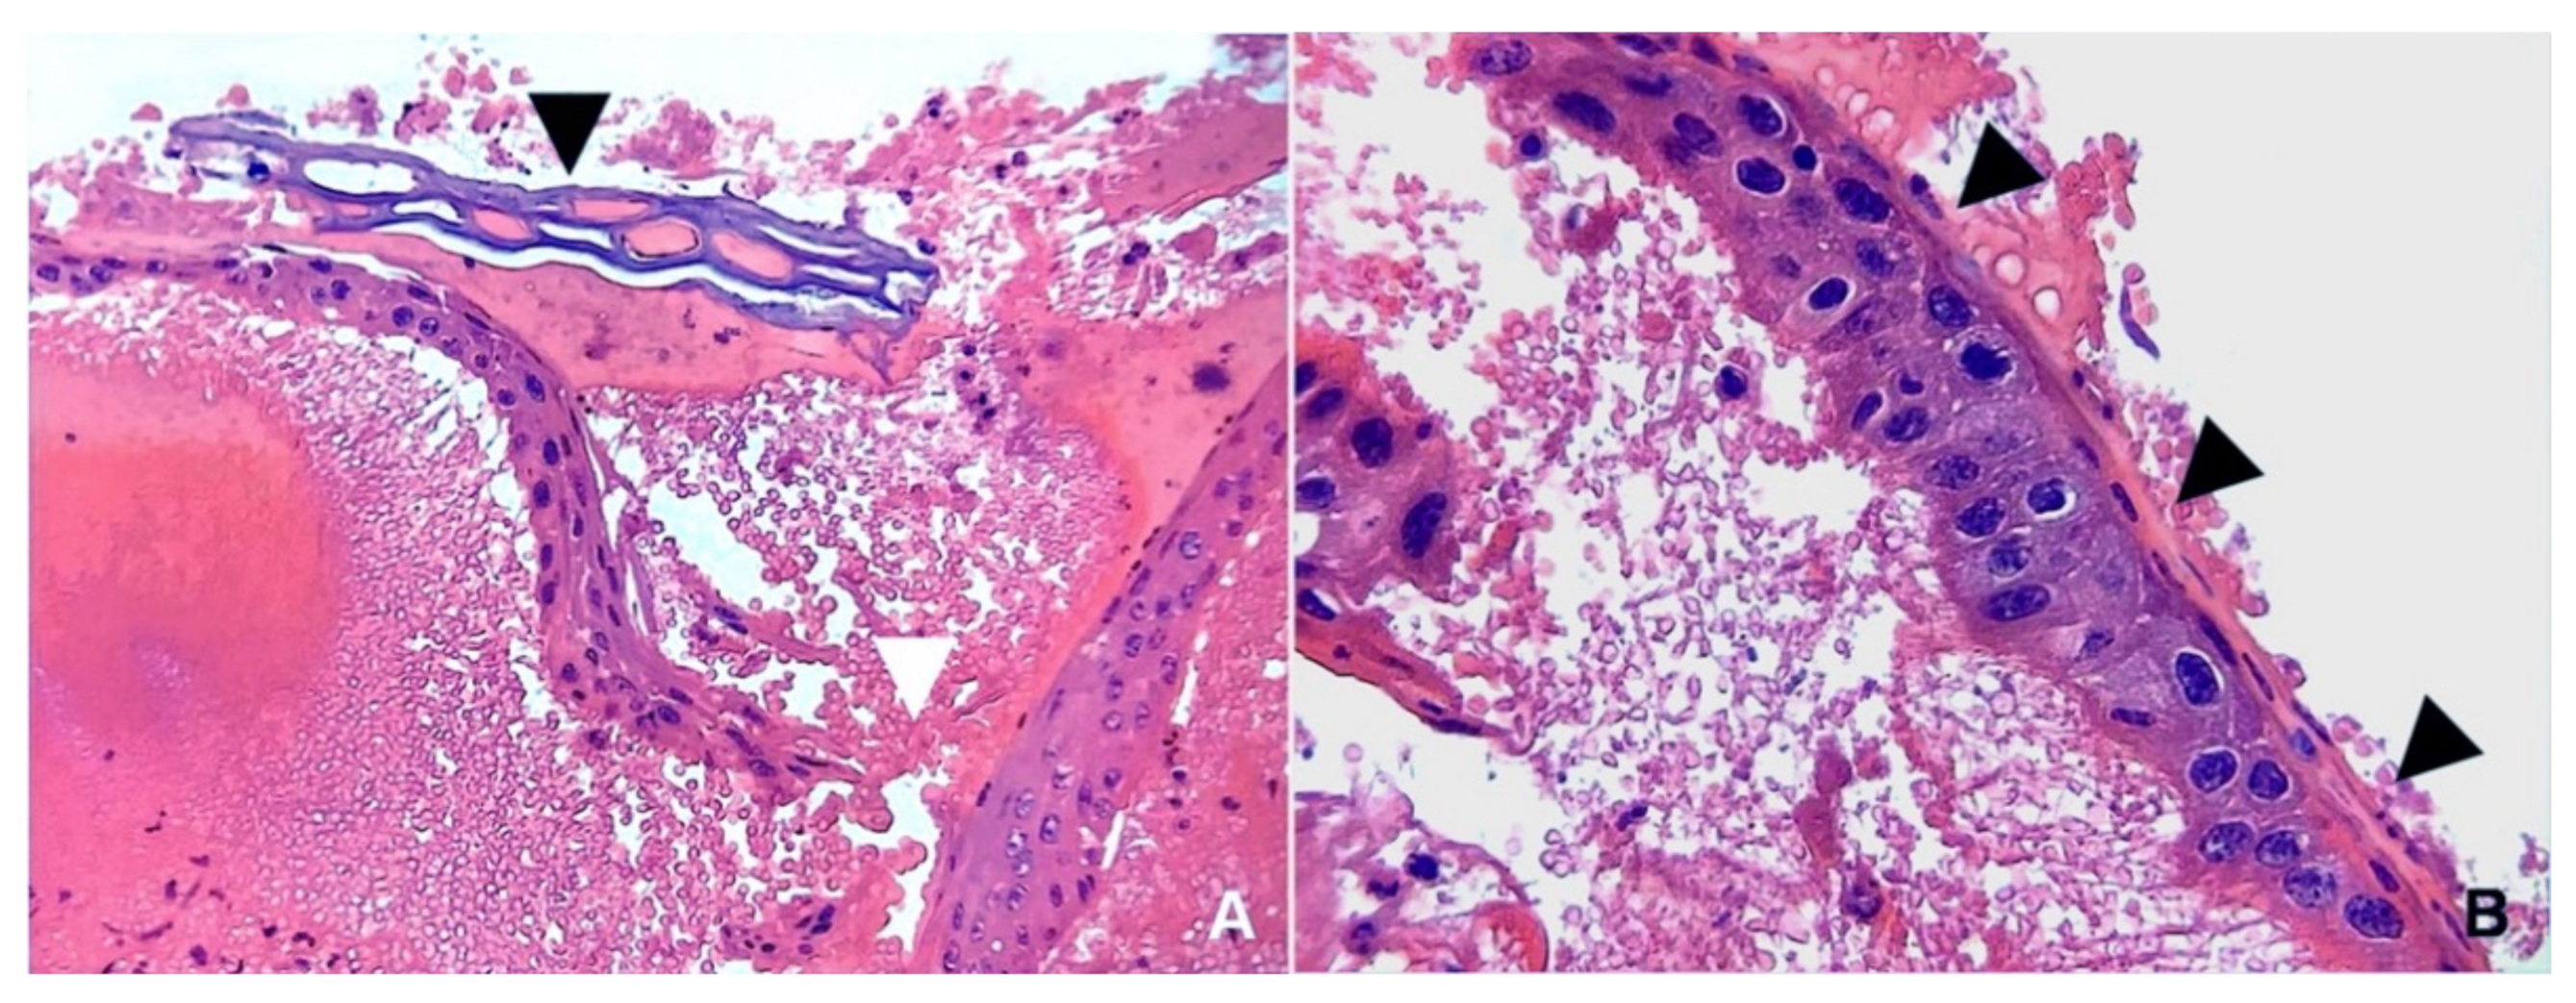

Importantly, multiple foci of mineralization were observed, scattered throughout the lung parenchyma and occasionally within the tracheal mucosa. In particular, the alveolar spaces were mainly affected, appearing as calcified casts of this portion of the respiratory tract (Figure 5).

Figure 3. Trachea. (a) The lamina propria appears hemorrhagic and a large amount of blood also covers the tracheal epithelium. This appears focally disrupted (white arrowhead) and thickened. In detail, the tracheal epithelium is stratified, with surface cell layers being flattened (squamous metaplasia). Vegetable cells are evident and close to the tracheal mucosa (black arrowhead). Such findings support the incidental inhalation of foreign substances (HE, magnification ×100). (b) At a closer view, the squamous metaplasia of the tracheal epithelium (black arrowhead) can be better appreciated (HE, magnification ×200).